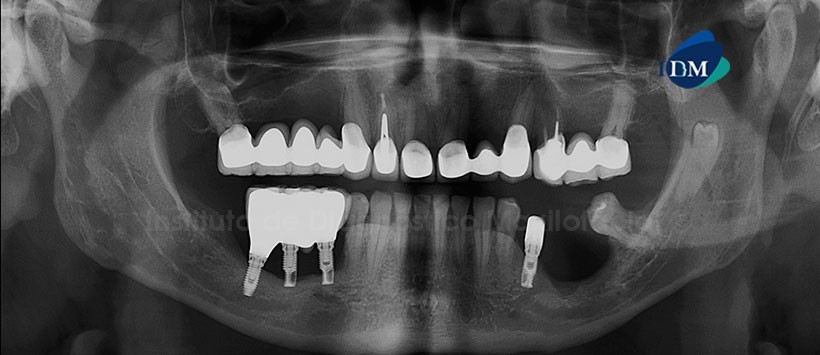

A la evaluación de la radiografía panorámica, se observa una reabsorción severa del proceso óseo dentoalveolar de ambos maxilares, múltiples coronas protésicas y presencia de implantes con prótesis sobre implantes. Siendo lo más resaltante la presencia de un diente supernumerario localizado en la rama mandibular de lado izquierdo próximo al conducto dentario inferior.

En la reformación panorámica obtenida mediante la tomografía volumétrica de haz cónico, se confirmó la presencia de esta pieza dentaria así mismo en los cortes transaxiales y tangenciales se pudo observar que se encuentra en una posición equidistante en relación a ambas tablas óseas. También se pudo evidenciar que esta pieza se encuentra próxima a la cortical superior del conducto dentario inferior.